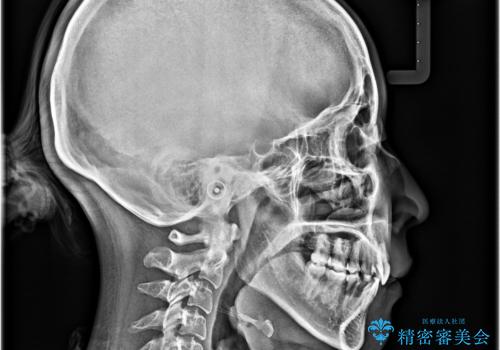

上下の前歯が接触する仕上がりとなったので、横顔の印象が大幅に改善されました。